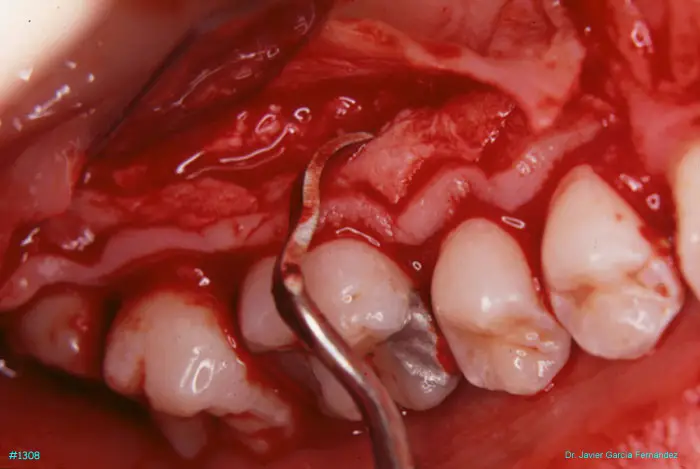

Atlas of Surgical Techniques in Periodontics. Chapter III. Atlas de Técnicas Quirúrgicas en Periodoncia